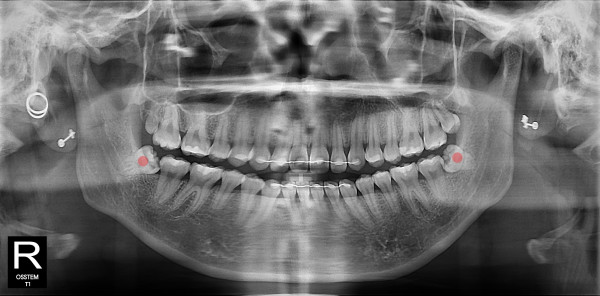

사랑니발치 10대/여성

5e20e086184bc11a2d853605b7813944_1764319875_2448.jpg